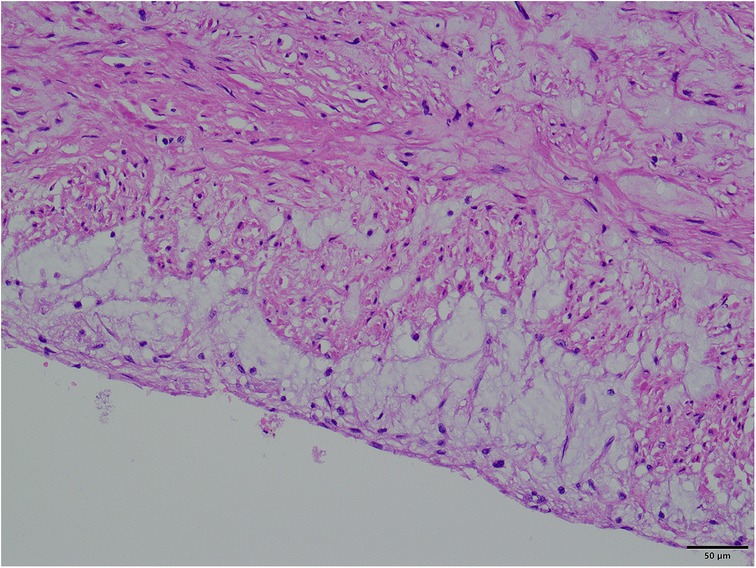

Figure 1

A giant aortic dissecting aneurysm. Contrast medium was observed to leak from the false lumen (red arrow).

A 45-year-old female patient, with a height of 155 cm and a low weight of 42 kg, was admitted to the hospital due to severe chest and back pain that had persisted for 9 h. The patient had undergone mechanical aortic valve replacement and aortic arch coarctation repair at our hospital 20 years earlier (the two operations were performed concomitantly). She had been taking warfarin for long time. She rarely received follow-up after surgery. Upon admission, the patient exhibited significant pain symptoms, accompanied by chest tightness, shortness of breath, and difficulty breathing; however, her vital signs were relatively stable, with a heart rate of 90–100 beats per minute. The physical examination revealed obvious surgical scars on the chest and left side of the thorax. Mechanical valve opening and closing sounds could be heard in the precordial area, along with a 3/6 grade systolic murmur. The electrocardiogram showed sinus rhythm, regular rhythm, and complete right bundle branch block. Echocardiography revealed a giant ascending aortic dissection aneurysm. The mean pressure gradient across the original mechanical aortic valve was 30 mmHg, with a peak gradient of 56 mmHg. The left ventricular diameter was 40 mm, the left atrial diameter was 19 mm, and the left ventricular ejection fraction (LVEF) was 70%. The enhanced computed tomography angiography (CTA) scan supported the presence of a giant ascending aortic dissecting aneurysm, with the largest cross-sectional area measuring approximately 101.3 × 85.2 mm (Figure 1). Contrast medium was observed to leak from the false lumen (Figure 1). The patient was slender, and the aneurysm occupied almost the entire anterior and posterior mediastinum (Figure 2A), severely compressing the heart (Figures 2B,C).